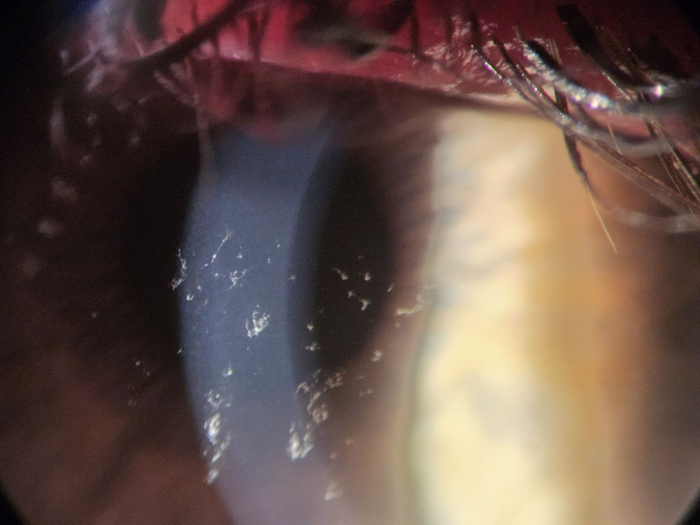

Тайский эксперимент с постакне-пятнами

Тайские дерматологи собрали 72 человека с лёгким и умеренным акне, у всех остались эритемы (красные пятна) и пигментация (коричневые пятна) — этакие памятники прошлым прыщам. Половину участников намазали гелем с 15-процентной азелаиновой кислотой, половину — плацебо. Никаких других средств — только солнцезащитный крем. Курс — 12 недель.

Исследование было рандомизированным (распределение по группам — случайное), двойным слепым (ни пациенты, ни врачи не знали, кто получает настоящий препарат), плацебо-контролируемым (есть контрольная группа для сравнения). То есть по всем канонам доказательной медицины.

Замеры делали серьёзные: дерматоскоп, система VISIA (специальная камера с разными спектрами света, которая выявляет скрытую пигментацию), индекс PAHPI (числовая оценка тяжести пятен: размер, интенсивность, количество), Mexameter (уровень меланина и гемоглобина в коже), корнеометр (влажность рогового слоя), тевометр (трансэпидермальная потеря воды, то есть насколько хорошо кожа держит влагу, цел ли барьер), себуметр (уровень жирности кожи).

<a href="https://pmc.ncbi.nlm.nih.gov/articles/PMC11116308/" target="_blank" rel="nofollow noopener">Оценка следов от акне с помощью анализатора кожи VISIA и дерматоскопии</a>

Оценка следов от акне с помощью анализатора кожи VISIA и дерматоскопии

К концу 12-й недели кожа в группе азелаиновой кислоты вздохнула с облегчением. Эритемы стали заметно бледнее и меньше по площади, общий индекс PAHPI упал почти вдвое. Пигментация тоже сдала позиции: интенсивность цвета упала наполовину, размер и количество коричневых пятен уменьшились, уровень меланина в коже снизился, пятна заметно посветлели.

При этом физиология кожи не пострадала, а даже улучшилась. Влажность рогового слоя повысилась примерно на четверть. Трансэпидермальная потеря воды осталась стабильной — барьер остался целым. Жирность кожи снизилась, а это значит меньше питания для бактерий, меньше риска новых воспалений.

Качество жизни участников выросло: индекс DLQI упал с умеренного влияния (когда пятна реально мешают) до минимального (когда они почти не беспокоят). В группе плацебо изменения были минимальными или вообще отсутствовали.